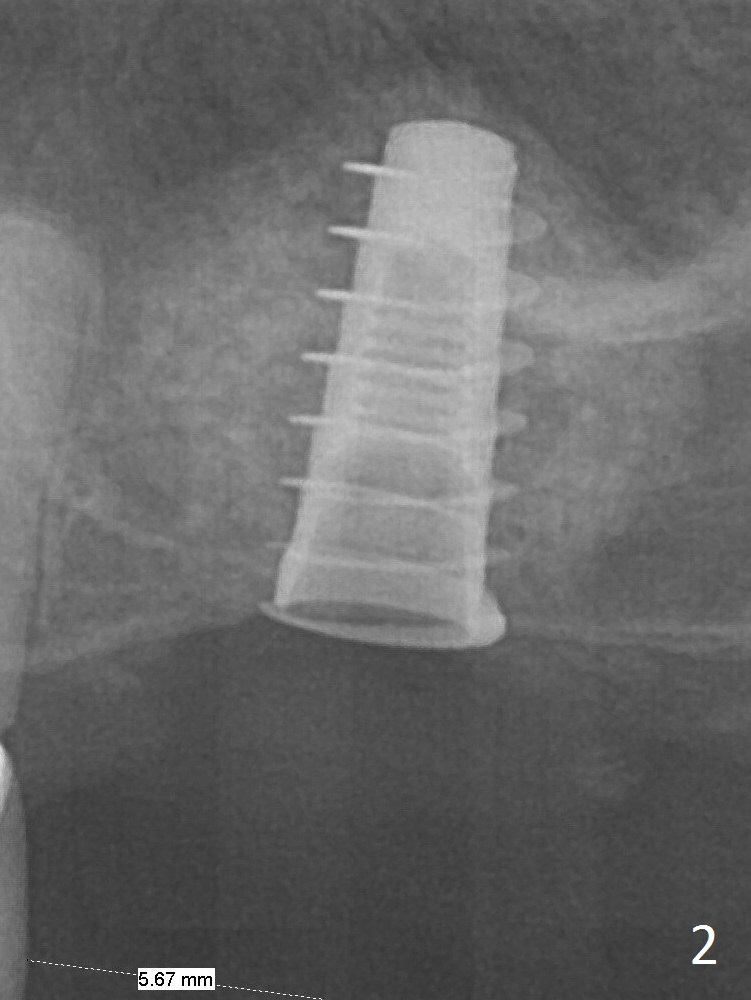

Magic Sinus Lifter is used to elevate the sinus floor for ~ 5 mm, followed by insertion of allograft/Osteogen and 4.0x11 mm dummy implant partially (Fig.1). With approximately 10% more of graft being placed, a 4.5x9 mm IBS implant is placed with insertion torque of 15 Ncm (Fig.2). The implant has a tenting effect. The bone graft appears to move distal 1 month 20 days postop (Fig.5 arrow), while the implant seems to be extruded with implant exposure. The patient feels pain when the healing screw is being removed or tightened. The distal migration of the bone graft may lay foundation for future implant placement at #15. Can the implant at #14 be retorqued to be seated deeper 3-4 months later? Bone density around the implant remains the same (Fig.6), while the wound reduces nearly 3.5 months postop (Fig.7). There are two layers of the bone, one (1) being denser than the other (2) 8 months postop (Fig.8). After local anesthesia, the healing screw is removed; the implant is found to be stable. A 6x4(2) mm pair abutment cannot be inserted due to blockage of the mesiobuccal gingiva (Fig.9 *). Instead a 6x2 mm healing abutment is placed. Three weeks later (approximately 8.5 months postop), the implant is found to be able to rotate when a 6.5x5.7(1) mm pair abutment is tightened with local anesthesia (there is pain associated with healing screw removal). After removal of the latter, the implant is placed deeper by hand retightening (Fig.10 arrow). Is it a better idea to use a new larger implant instead? The patient (53 years old) is scheduled to return for follow up in 3 months.